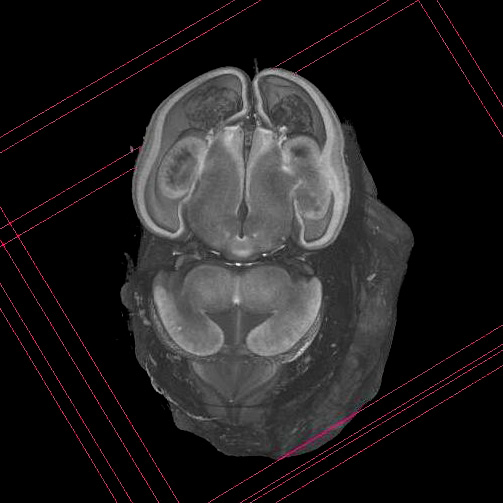

Histology Sections

eHistology viewer

Kaufman Atlas of Mouse Development